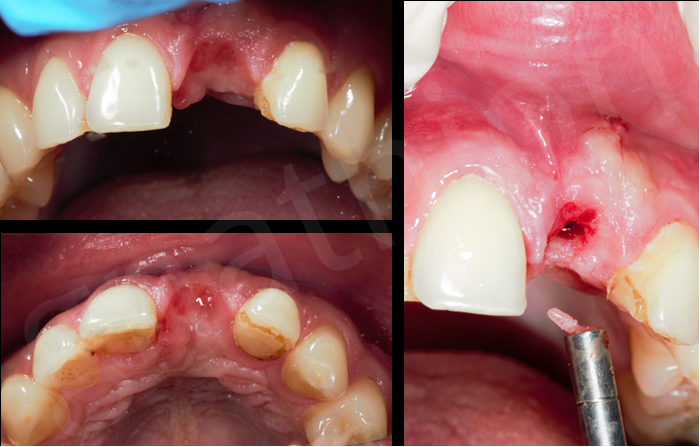

Μετά απο 5 μήνες έγινε «αποκάλυψη» του εμφυτεύματος και κατασκευάστηκε προσωρινή στεφάνη η οποία παρέμεινε κοχλιωμένη για 3 ακόμη μήνες έτσι ώστε να προσαρμοστούν πιο αρμονικά και αισθητικά οι μαλακοί ιστοί της περιοχής στην προσθετική υπερκατασκευή του εμφυτεύματος(Εικόνες 3 και 4).